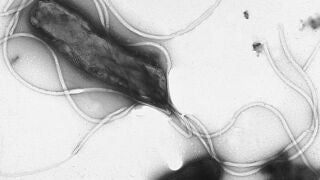

Más de la mitad de la población convive con la bacteria Helicobacter pylori sin presentar síntomas, aunque en algunos casos puede provocar enfermedades digestivas como gastritis, úlceras o cáncer gástrico.

Ardor de estómago, digestiones pesadas o molestias abdominales tras las comidas son síntomas que muchas personas normalizan en su día a día. Sin embargo, detrás de estas molestias aparentemente comunes puede encontrarse la Helicobacter pylor, la infección bacteriana crónica más frecuente en humanos, que afecta a casi la mitad de la población mundial.

Esta bacteria tiene la capacidad excepcional de sobrevivir en el ambiente extremadamente ácido del estómago, algo poco habitual para los microorganismos. Según explica la doctora Malena García Arredondo, neurogastroenteróloga, experta en trastornos del eje intestino-cebro y directora de MGA Healthy Digest, unidad de aparato digestivo y microbiota en Memorial Publio Cordón Hospital en Pozuelo de Alarcón, la infección suele adquirirse en la infancia y puede permanecer latente durante décadas sin provocar síntomas claros, lo que facilita su propagación silenciosa.